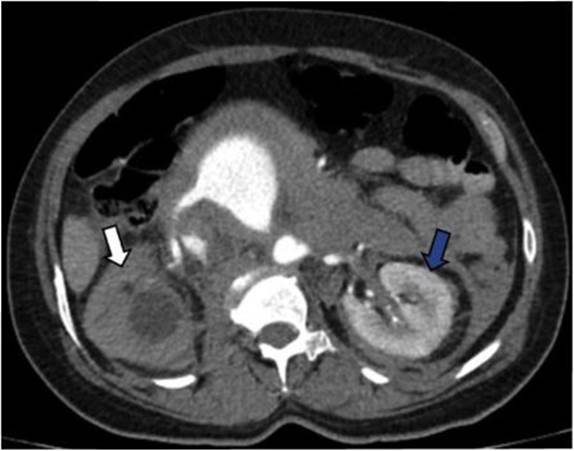

Fue posible identificar la extensión del aneurisma abdominal hasta la bifurcación de las arteria ilíacas adyacente a la VCI en todo su recorrido abdominal (Figura 2). Adicionalmente se observó ausencia de realce del parénquima renal derecho por hipoperfusión y cambios inflamatorios periaórticos con hematoma retroperitoneal asociado (Figuras 3 y 4).

Signos adicionales que soportan FAC son la hipoperfusión renal y la ruptura del aneurisma 5. El trabajo de Navdeep Singh y colaboradores concluyó que la presencia simultánea de contraste en la aorta y la VCI durante la fase arterial es el signo diagnóstico más importante; sin embargo, muy a menudo el aneurisma comprime la VCI, lo que dificulta la evaluación de este signo 5.